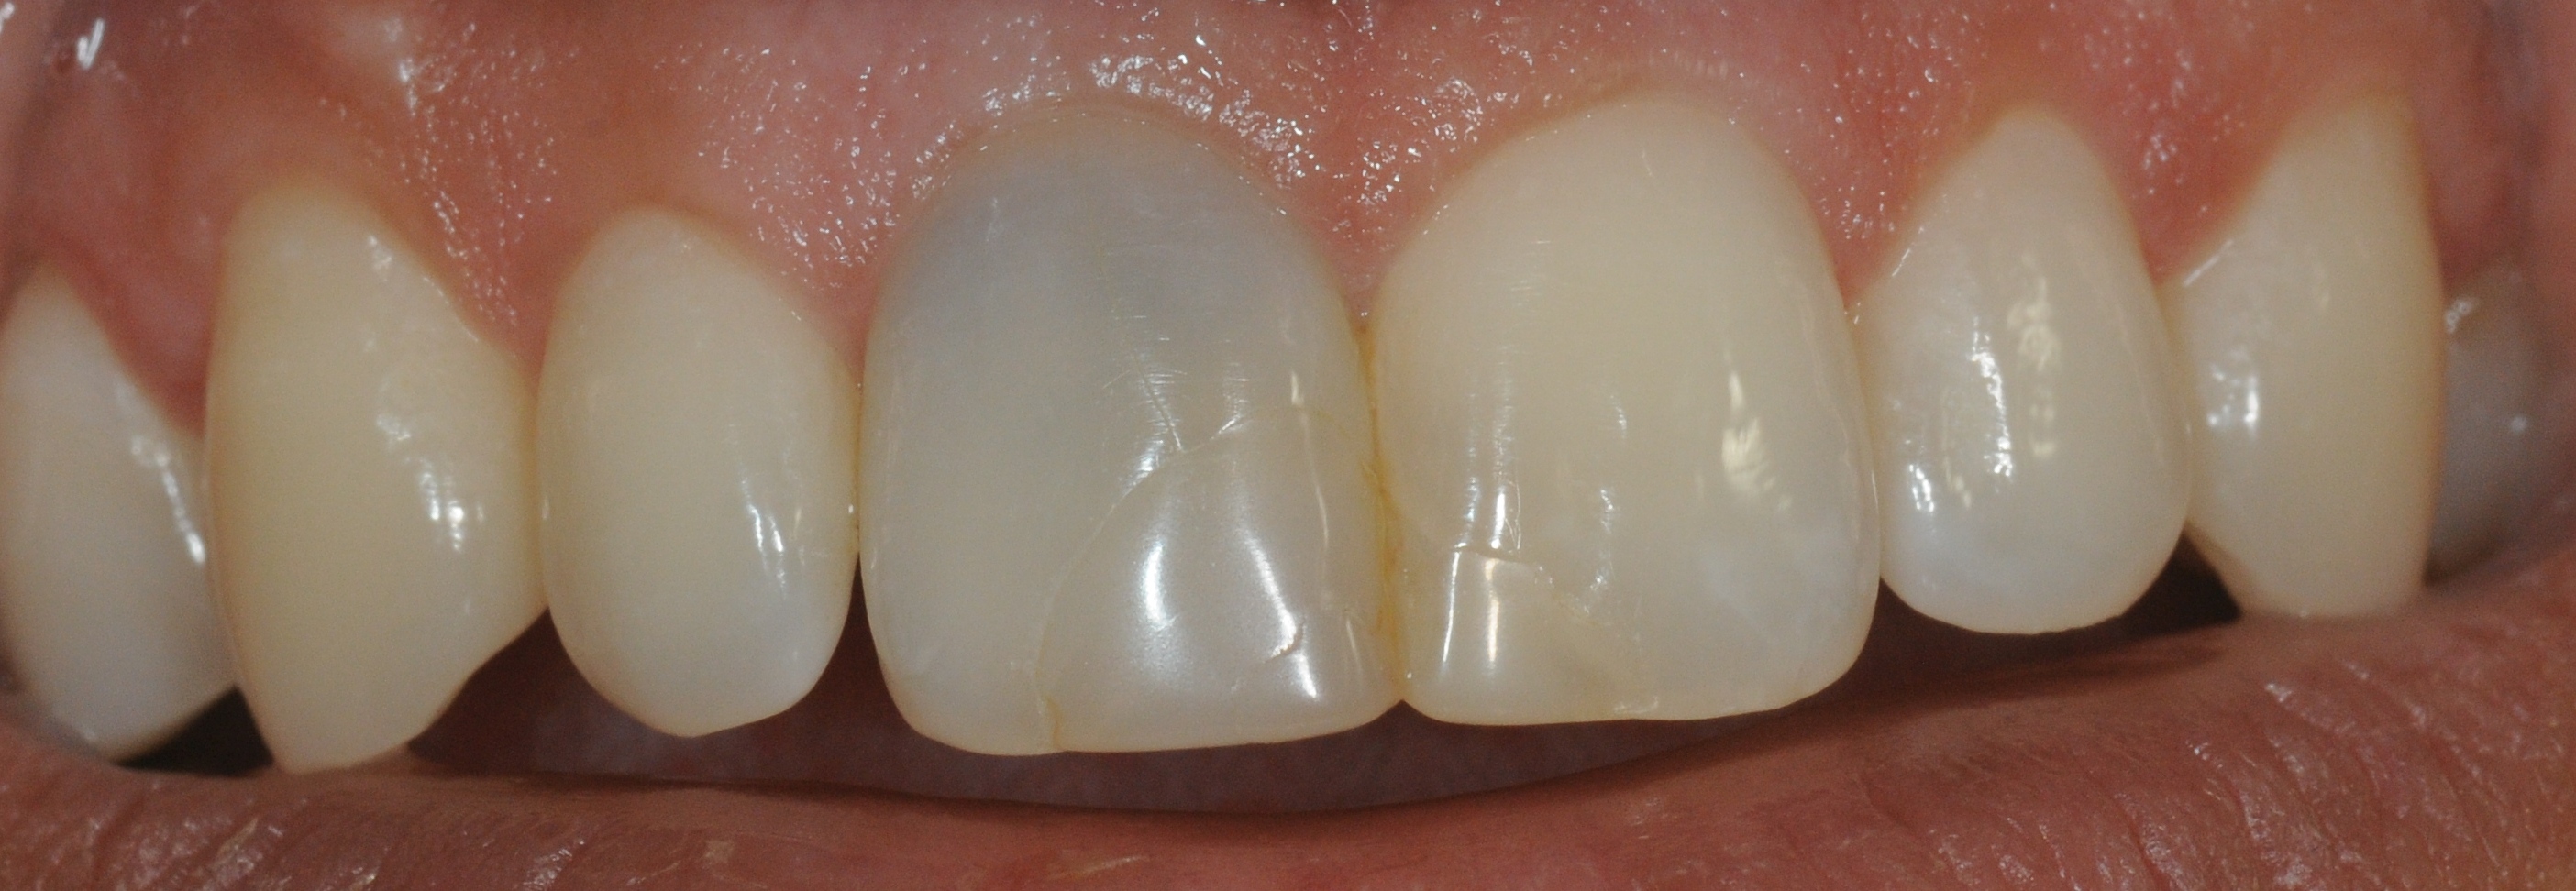

Wurzelbehandelte Zähne können dunkel werden, weil sich Farbstoffe im Zahn einlagern.

Wir haben die Möglichkeit, diesen von innen heraus zu bleichen.

Zustand nach einer Woche Bleicheinlage. Der Zahn kann nun mit einer definitiven Füllung versorgt werden.

Es wird auch oft gefragt, wie lange denn der Bleicheffekt anhält. Beim Bleichen werden Farbstoffe, die sich in den Zahn eingelagert haben optisch inaktiviert. Danach sollten eigentlich keine weiteren Farbstoffe mehr da sein, somit sollte das Bleichergebnis dauerhaft sein. Wir haben mittlerweile Langzeitergebnisse von über 17 Jahren. Das Ergebnis hat sich nicht verändert.

Hier ist aber auch deutlich zu sehen, was Internes Bleichen (Bleaching) nicht kann: vorhandene Füllungen bleiben wie sie sind und kommen durchs Bleichen stärker zur Geltung. Diese müssen dann gegebenenfalls getauscht werden, um die Farbe an den gebleichten Zahn anzupassen. Das gleiche gilt für Verfärbungen als Auflagerungen auf dem Zahn, diese werden im Rahmen der Zahnreinigung wegpoliert.